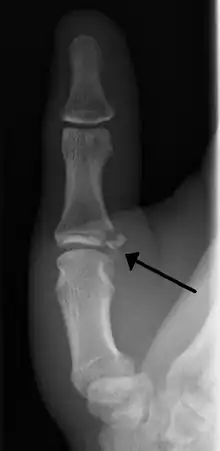

Avulsion fractures of the ulnar base of the proximal phalanx of the thumb ( Gamekeeper's fracture )

When approaching this type of injury, the physician must first determine whether there is an incomplete rupture (or sprain) of the UCL, or a complete rupture. If the UCL is completely disrupted, the physician must then determine whether there is interposition of the adductor aponeurosis (Stener lesion), or simply a complete rupture of the UCL with anatomic or near-anatomic position. Radiographs are helpful in determining the possible presence of an avulsion fracture of the proximal phalanx insertion site of the ulnar collateral ligament. Stress examination, or one done under fluoroscopic guidance, can help determine the integrity of the ligament.